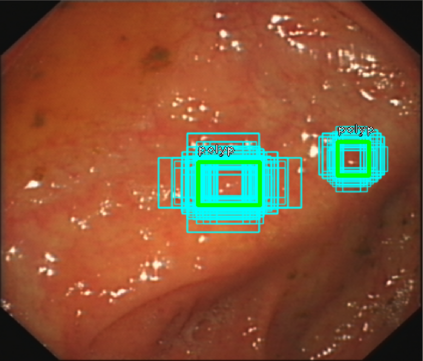

We improved an existing end-to-end polyp detection model with better average precision validated by different data sets with trivial cost on detection speed. Previous work on detecting polyps within colonoscopy \cite{Chen2018} provided an efficient end-to-end solution to alleviate doctor's examination overhead. However, our later experiments found this framework is not as robust as before as the condition of polyp capturing varies. In this work, we conducted several studies on data set, identifying main issues that causes low precision rate in the task of polyp detection. We used an optimized anchor generation methods to get better anchor box shape and more boxes are used for detection as we believe this is necessary for small object detection. A alternative backbone is used to compensate the heavy time cost introduced by dense anchor box regression. With use of the attention gate module, our model can achieve state-of-the-art polyp detection performance while still maintain real-time detection speed.